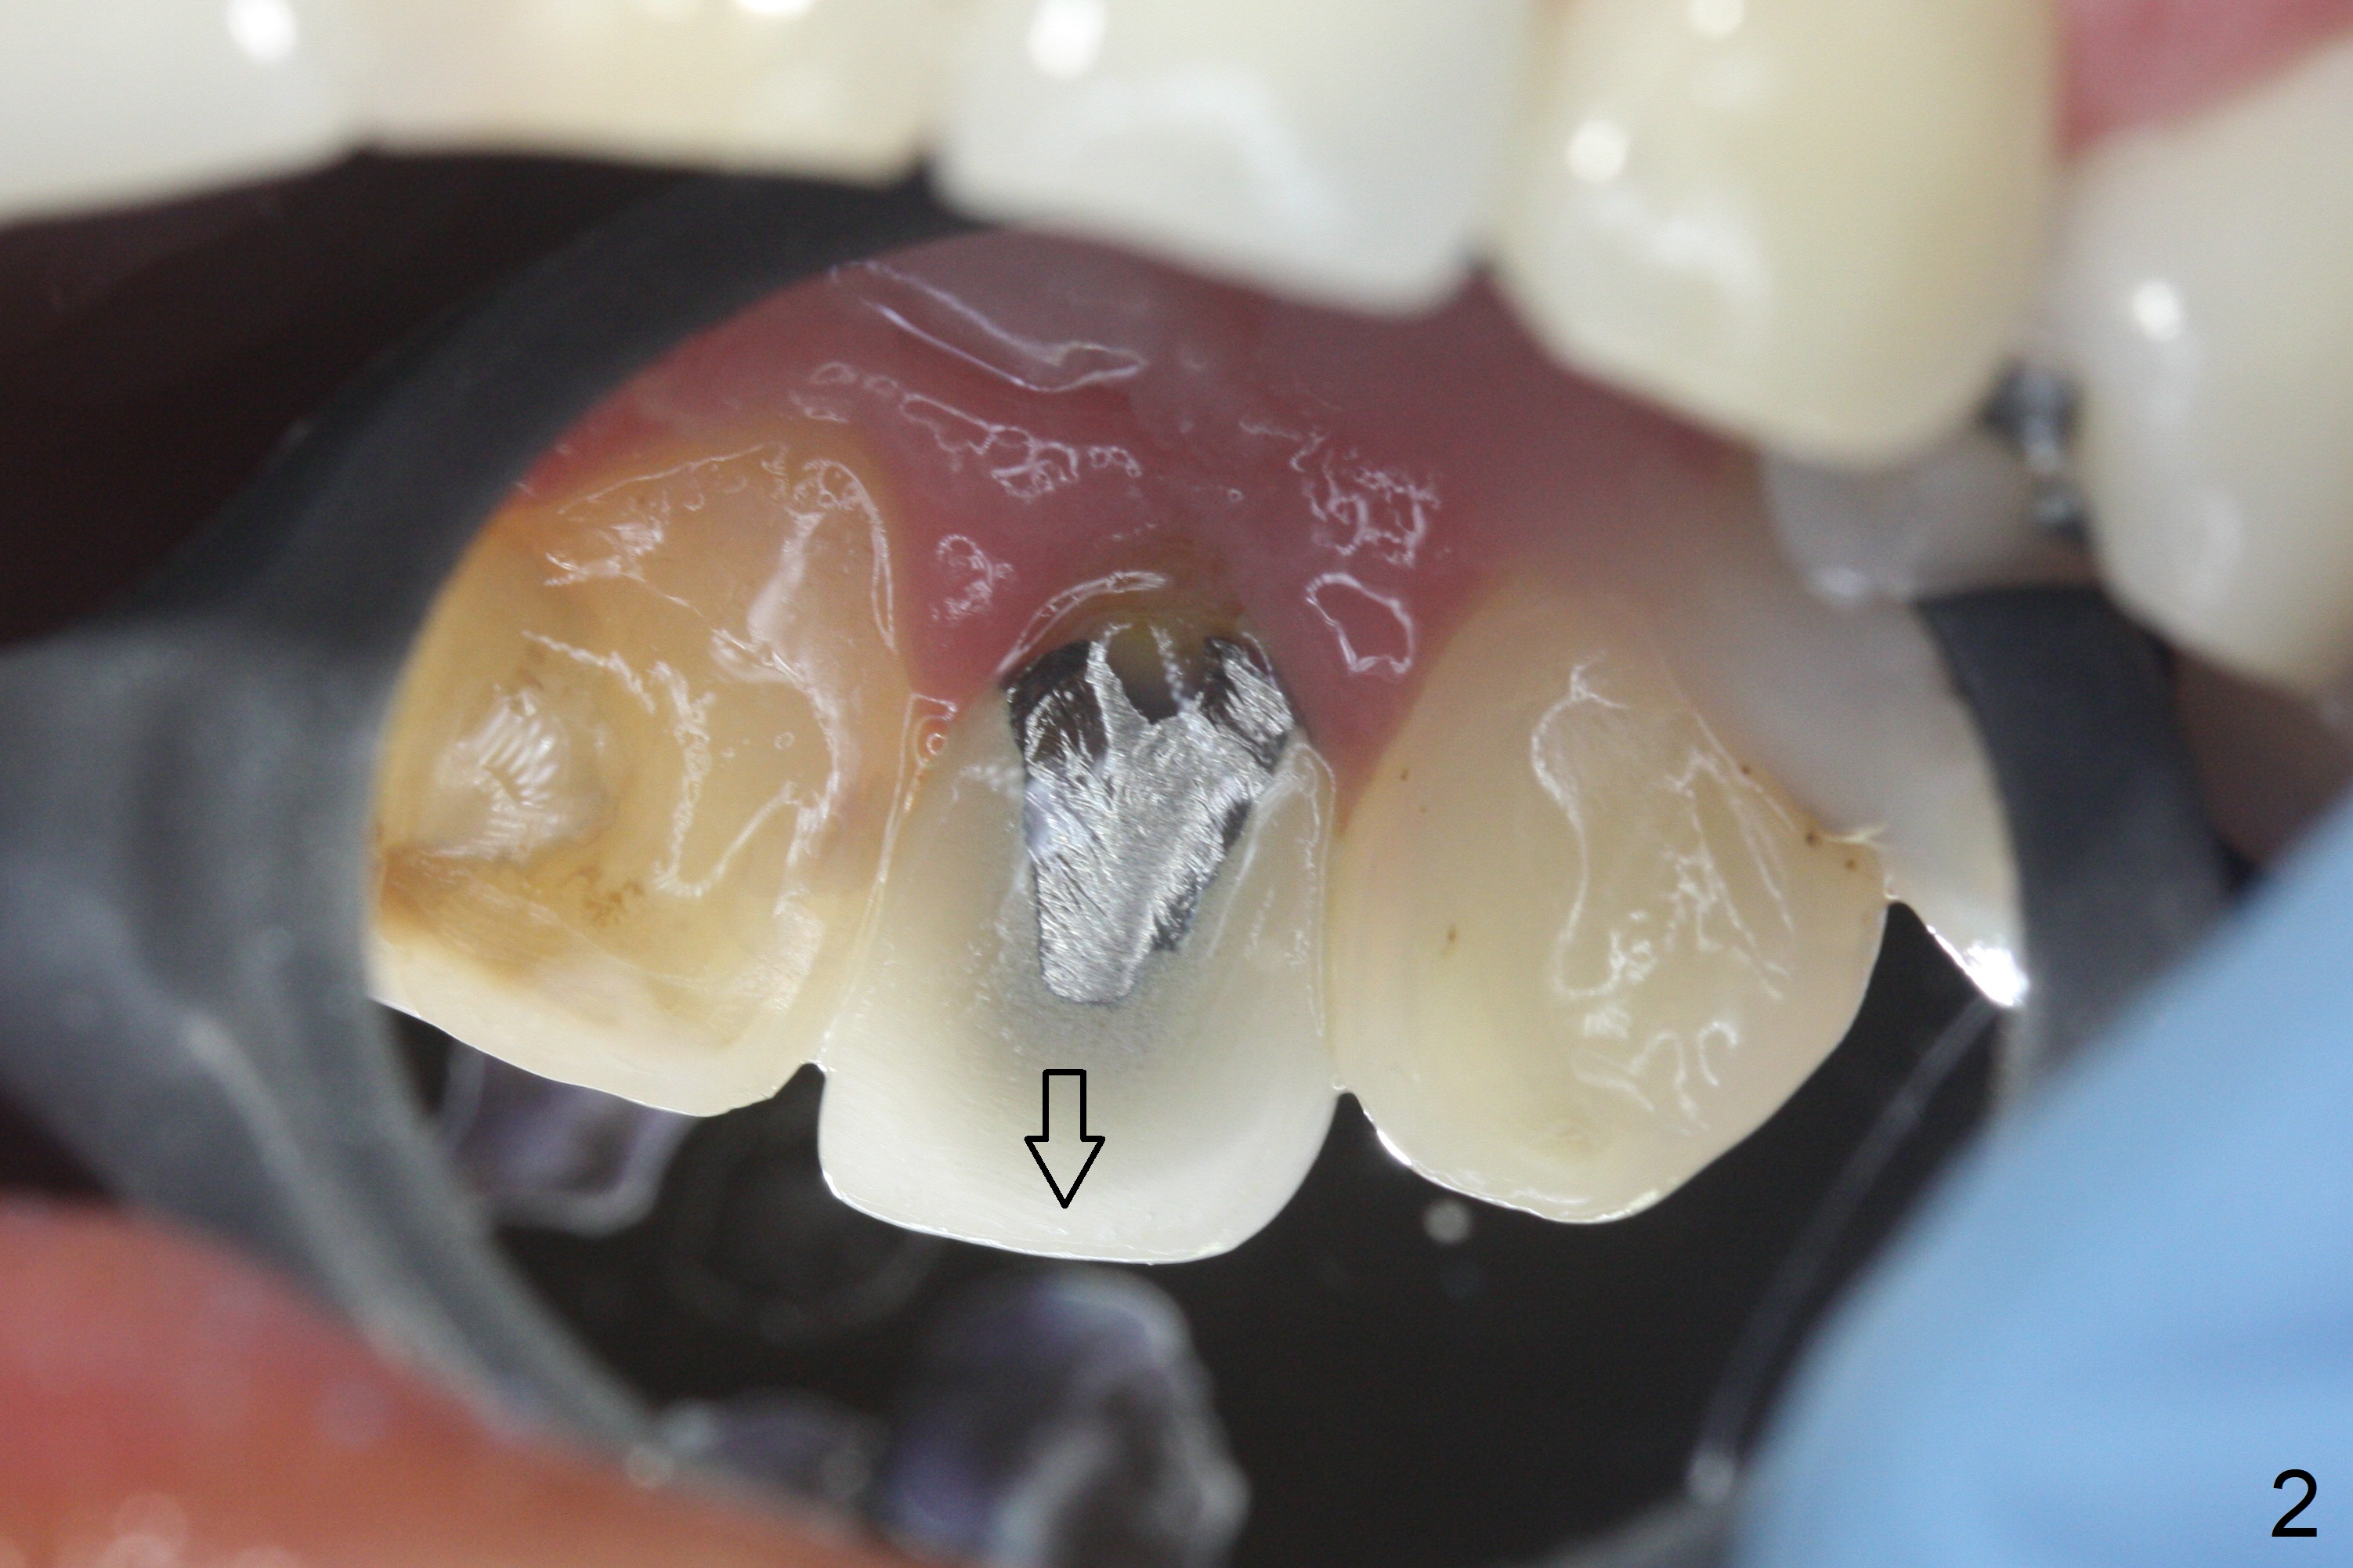

When the patient returns, the crown at #10 has displaced incisally (Fig.1,2 arrow). The initial depth is 15 mm (Fig.3, palatal gingival margin). After a 3.8x12 mm SM implant is placed (Fig.4), allograft is packed in the peri-implant space (*, as compared to Fig.3) and a 3.9x4(3) mm abutment is placed (A). More allograft is placed in the peri-abutment space (Fig.6 *). The existing crown (Fig.4,5 C) is hollowed, relined (R) and used as an immediate provisional (Fig.7-9). The patient is pleased with the appearance of the apically-repositioned provisional (Fig.7 arrow). She returns for impression 3.5 months postop (Fig.10). After change of abutment to 3.9x4(4.5) mm and new provisional, impression is retaken 5 months postop (Fig.11,12). It appears that the implant is palatally placed and a little large for the site (Fig.11 (B: buccal); Fig.12 (^: thin layer of the palatal plate)). If an angled abutment were used, a screw-retained crown might have been feasible. Due to the new provisional, the gingiva looks healthy when a permanent crown is cemented (Fig.13).